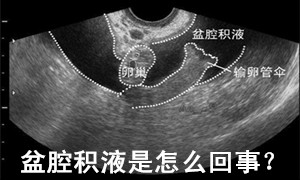

盆腔积液是怎么回事? 因为盆腔是腹腔在全身最低的部位,当有渗出液或漏出液时都会引流到盆腔,从而形成盆腔积液。大多数盆腔积液是由于炎症引起,即由慢性盆腔炎症渗出所致。盆腔积液的主要致病因有:月经期不注 意卫生、邻近器官炎症蔓延、产后、流产后感染、妇科手术后感染等。也有少数因宫外孕破裂、黄体破裂、盆腔脓肿、巧克力囊肿、卵巢癌引起。